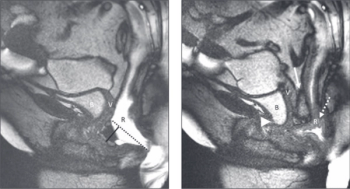

Findings suggest that patients with suspected axial spondyloarthropathy not taking NSAIDs were more likely to have MRI proven inflammation compared with patients taking NSAIDs.